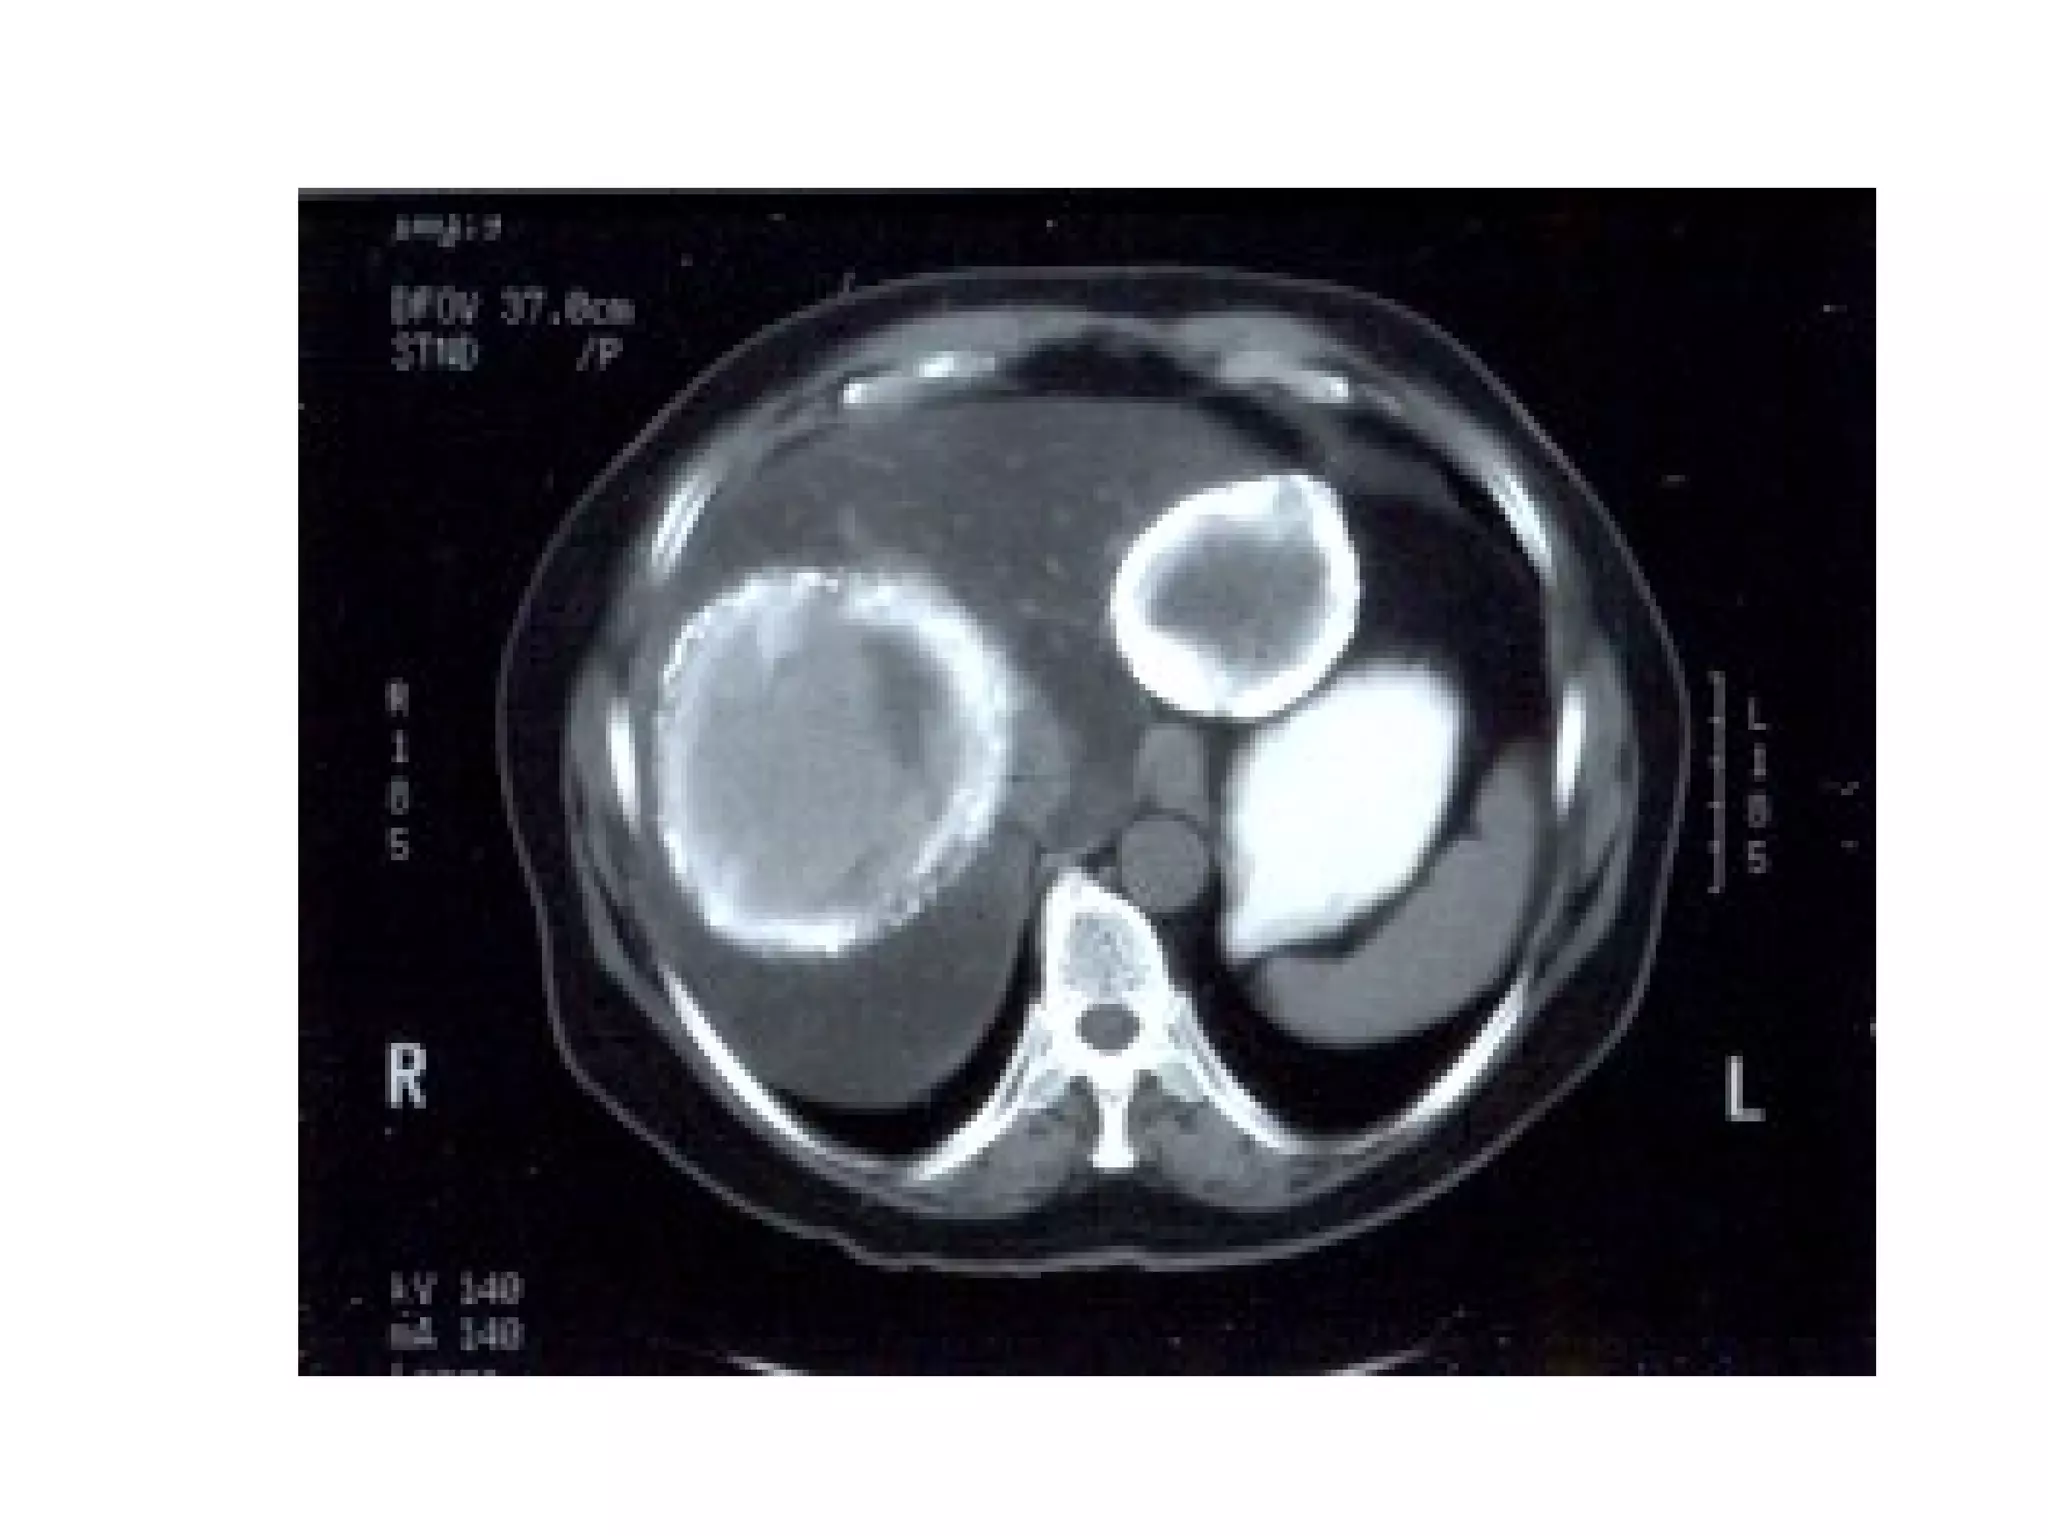

CysticerciCysticerci Hydatid CystHydatid Cyst

Isolated cysticerci Hydatid cyst

Cystic Hydatid Disease